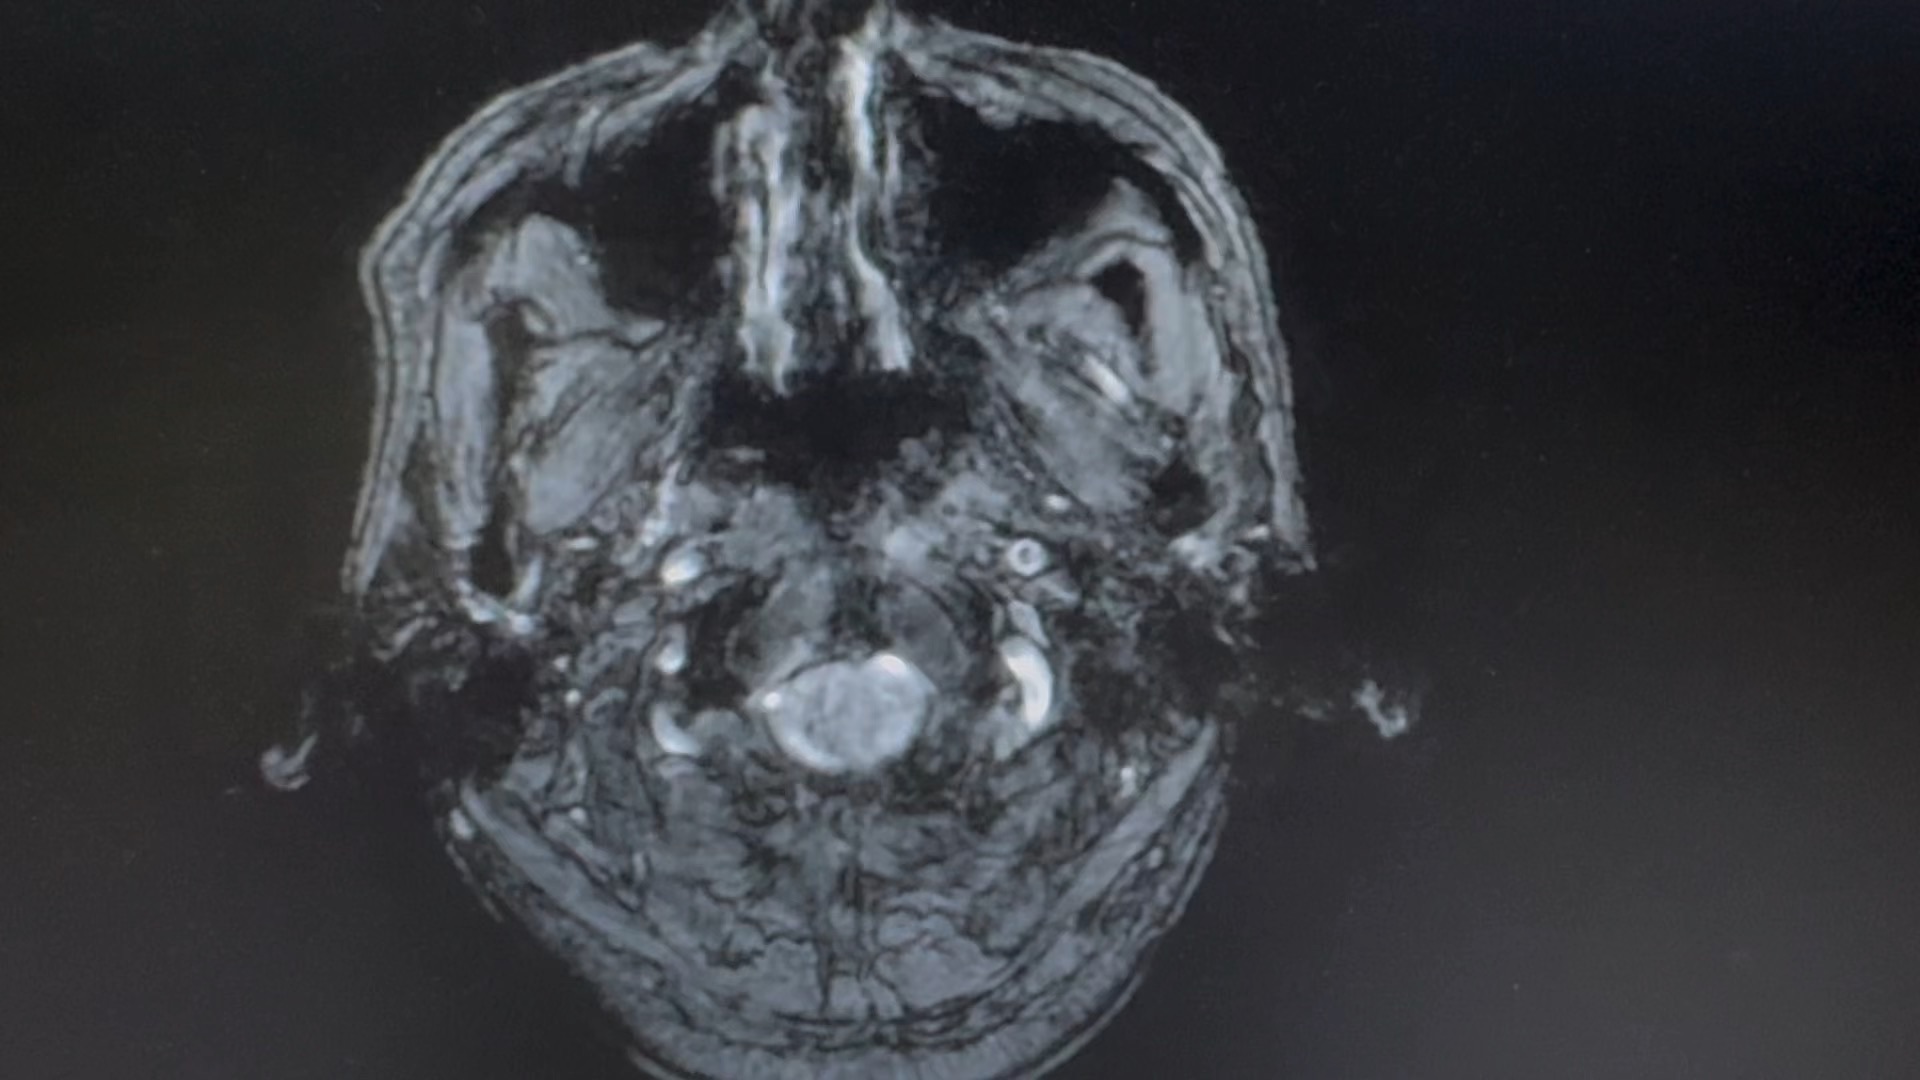

男,66 岁

突发剧烈头疼,呕吐伴意识模糊数小时。

一人在家,家属下班后发现患者情况不对,拨打 120 急诊入院,已转入脑介入科。